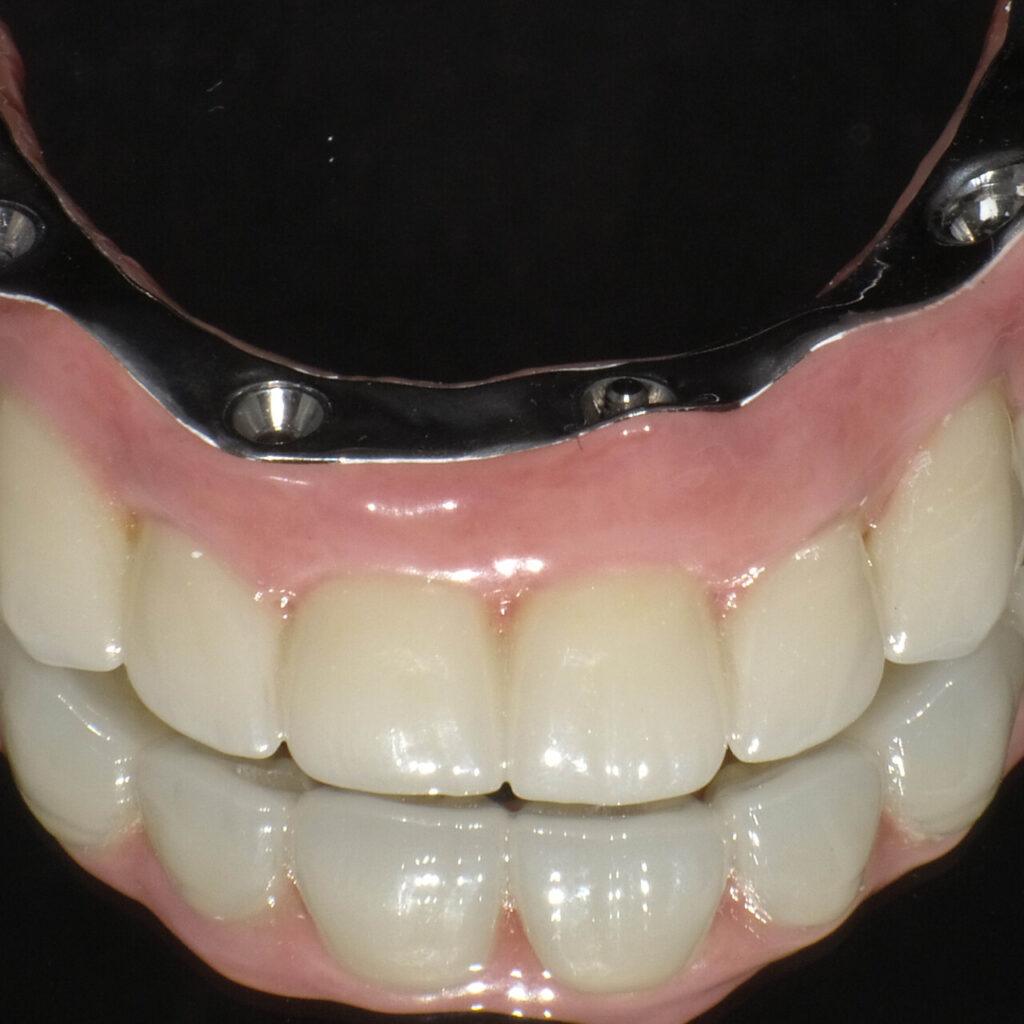

Zabieg 1-3hPo okresie gojenia (4-6 mies.) zakładamy stałe zęby. Wyglądają i działają jak naturalne. Jesz co chcesz, uśmiechasz się bez skrępowania. Nie chodzisz bez zębów ani jednego dnia.

Efekt na lataStałe zęby na 6 implantach zamiast ruchomej protezy. Wszystko zaplanowane z góry, bez niespodzianek.

Brakuje wszystkich zębów → SAFE ARCH (stałe zęby na 6 implantach)